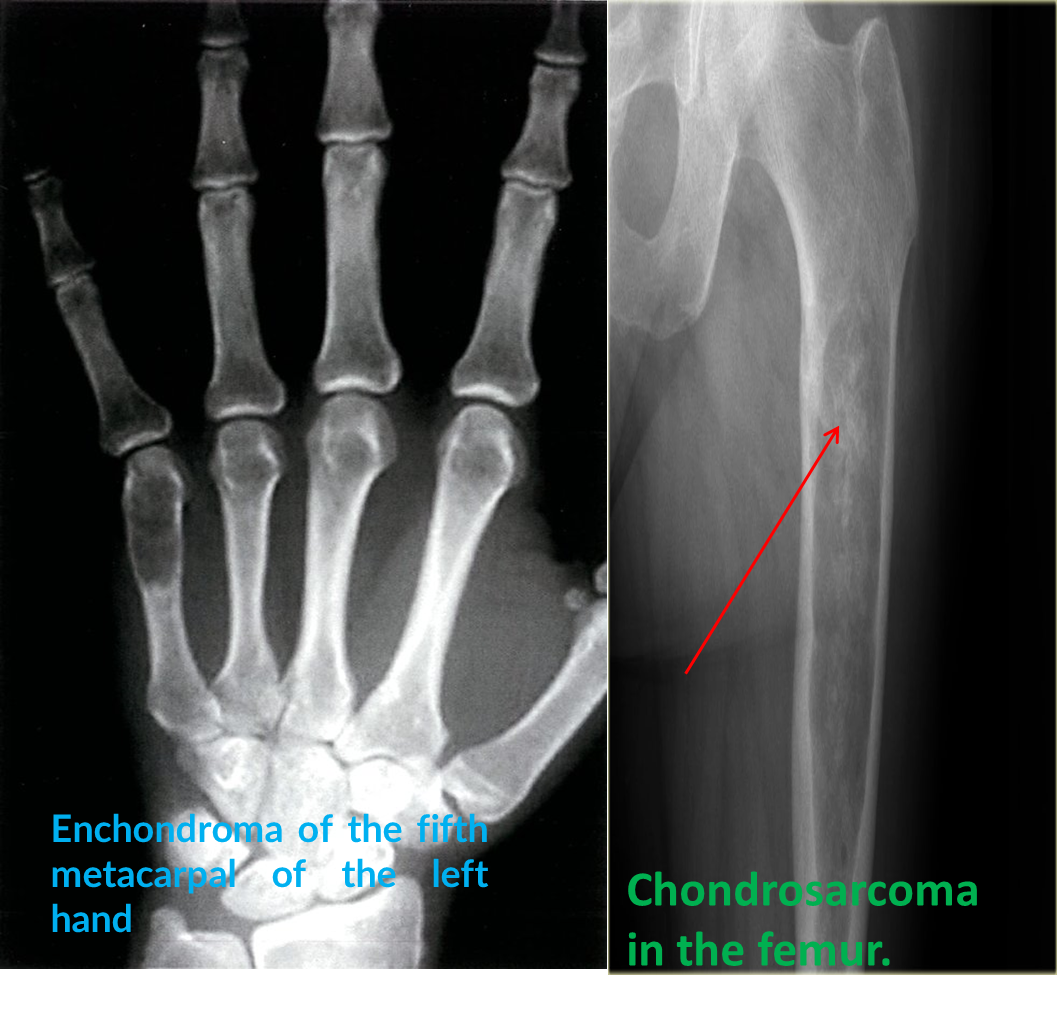

- Benign cartilage tumor

- Are seen as lytic expanding lesions, most commonly in the bones of the hand.

- They often contain a few flecks of calcium and frequently present as a pathological fracture.

Anteroposterior x-ray of the left hand: oval area of reduced bone density in the distal third of the fifth metacarpal bone